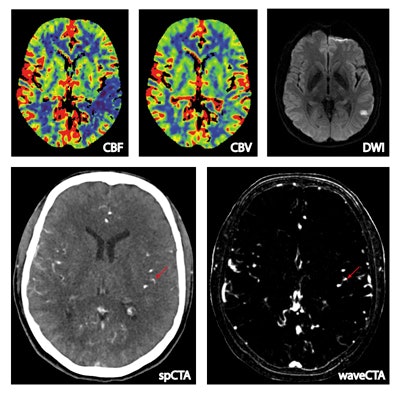

The wavelet transform of CT perfusion data is based on time-signal profiles (signal refers to HU values) of each voxel. Voxels with bolus flow time-signal profiles (upper arrows) are enhanced, whereas unspecific profiles (lower arrows) are suppressed. Note the higher detail visibility and contrast-to-noise ratio of small vessels. All images courtesy of Dr. Wolfgang Kunz.

Among the final study population of 63 patients, 31 had occlusions detected by wavelet CTA, most prominently in the middle cerebral artery (MCA), which yielded 48 cases, mostly on the M3 and M2 vessels, Kunz said. There were also smaller groups of anterior cerebral artery (ACA, n = 6) and posterior cerebral artery (PCA, n = 6) ischemias, among which wavelet CTP detected half, and finally three superior cerebellar artery occlusions, he said.

The study team also rated image quality of the vessels between the two modalities. "We didn't see any differences in image quality in the larger vessels, but there was a significant difference in smaller vessels in the M2-M4 in favor of wavelet CTA," Kunz said.

Wavelet CT angiography shows significantly higher detailed visualization of small vessels and vessel occlusions in 49% of patients with CT perfusion deficit, negative CT angiography, and confirmed stroke at follow-up CT or MRI, he continued.